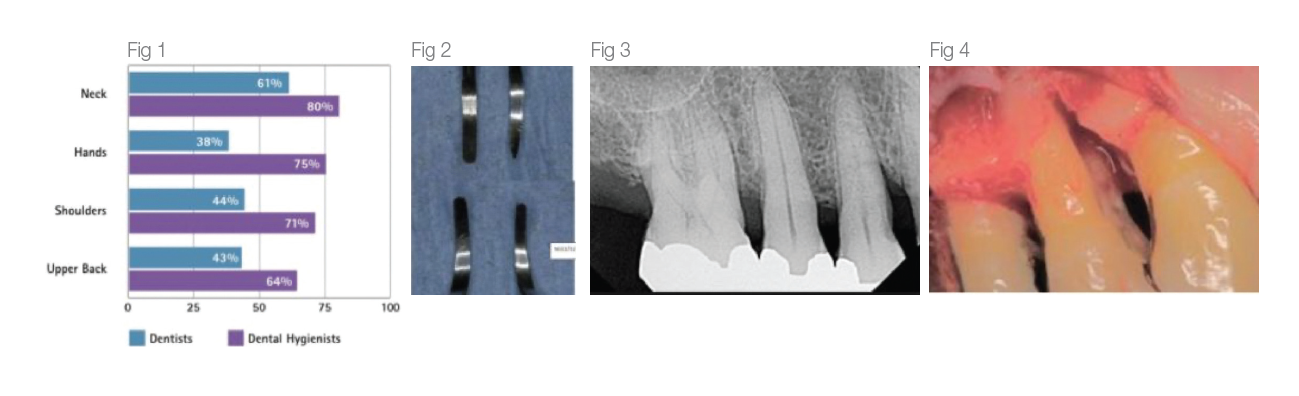

The Costs for the Clinician

A literature review2 conducted by Johnson and Kanji in 2016 states that 92% of Dental Professionals reported symptoms in at least 1 anatomical, upper body region in the past 12 months with Dental Hygienists being the group most affected (see Fig 1). Work related Musculo- skeletal Disorders (MSD) in dental hygienists are often blamed on repetitive movements, awkward and static postures, pinch- grasp, forceful exertions, vibration, poor ergonomics, and insufficient breaks amongst other factors.

The cost of burnishing calculus, resulting in iatrogenic and supervised progression of periodontal disease when patients are placing their oral health in our hands cannot be measured (Fig 3,4). Breakage of a blade in a patient’s mouth, with possible need for surgical intervention due to using an over-worn working end is a preventable situation with a simple and quick check of the working end against a template.